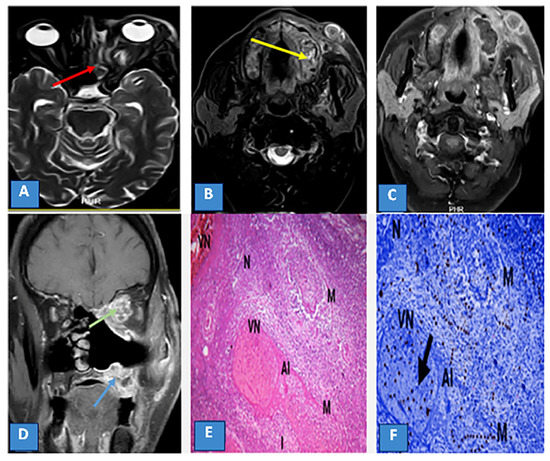

3.4. Extrasinus Extension

3.5. Histopathological Findings